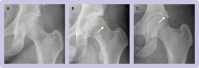

Participants: 222 participants aged 18 to 60 years with symptomatic FAI confirmed clinically and with imaging (radiography or magnetic resonance imaging) were randomised (1:1) to receive arthroscopic hip surgery (n=112) or a programme of physiotherapy and activity modification (n=110). Exclusion criteria included previous surgery, completion of a physiotherapy programme targeting FAI within the preceding 12 months, established osteoarthritis (Kellgren-Lawrence grade ≥2), and hip dysplasia (centre-edge angle <20 degrees).

Interventions: Participants in the physiotherapy group received a goal based programme tailored to individual patient needs, with emphasis on improving core stability and movement control. A maximum of eight physiotherapy sessions were delivered over five months. Participants in the arthroscopic surgery group received surgery to excise the bone that impinged during hip movements, followed by routine postoperative care.